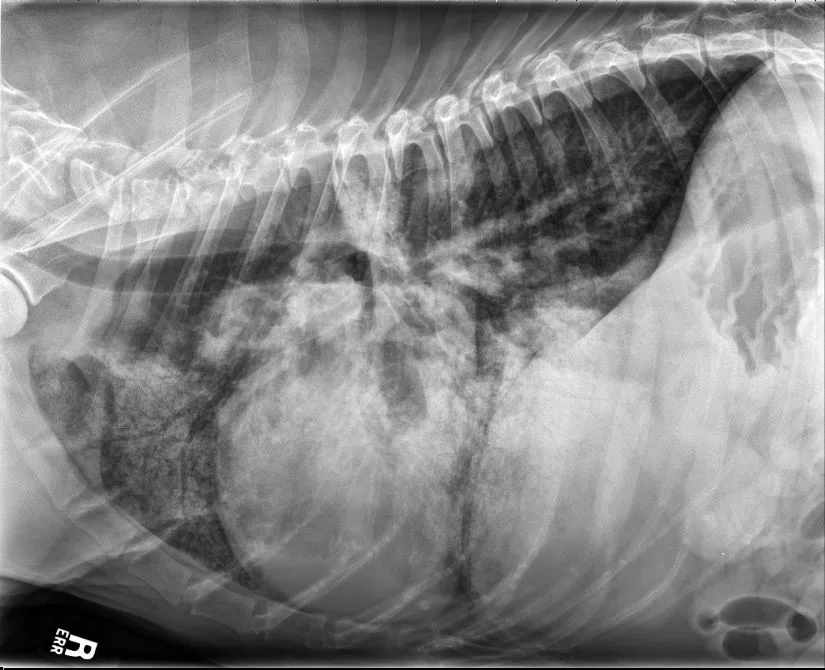

FIGURE 9 DV (left) and right lateral (right) projections consistent with left-sided CHF in a dog with advanced DCM. Perihilar to ventral distribution of the severe interstitial to alveolar pulmonary pattern is present in addition to cardiomegaly. VHS, VLAS, M-VLAS, and VRHi collected from the right lateral view are 11.5, 2.1, 4.1, and 3.1, respectively. (Note: The DV image is flipped to display the right side of the patient to the left.)